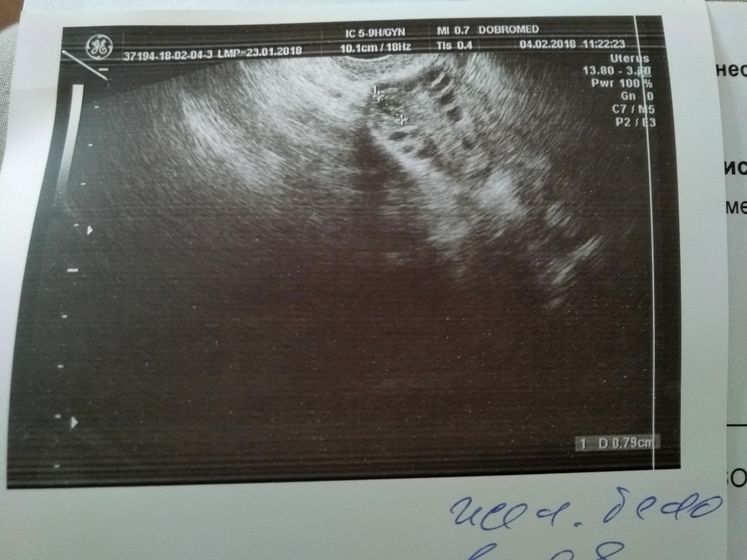

Поехали сегодня в пургу и вьюгу на УЗИ в Добромед(не в восторге) Сделали узи, рассказала что и как врачу, при осмотре было желтое тело, но как я поняла, не совсем то что нужно. В остальном все хорошо, матка, яичники все в норме. Критичного ни чего нет. Послали на ХГЧ завтра за результатом. Если есть, кто разбирается в заключении и в узи, буду рада информации. Тест все еще показывает //